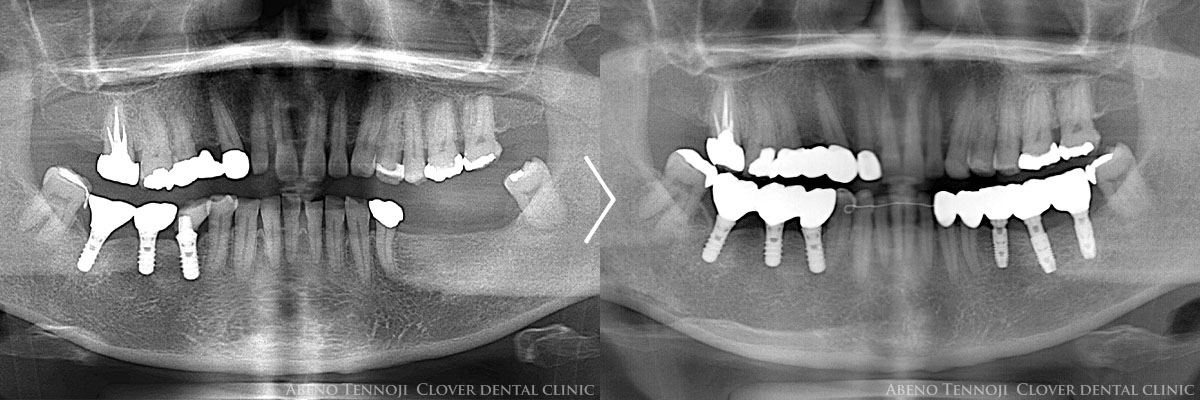

当院は、レッドダイヤモンドプロバイダーに6年連続で認定されている医院です。

レッドダイヤモンドプロバイダーとは、インビザラインの年間症例数が1000症例以上の医院に与えられる最高位の称号です。当グループは、年間症例数が西日本一で多くの実績があります。